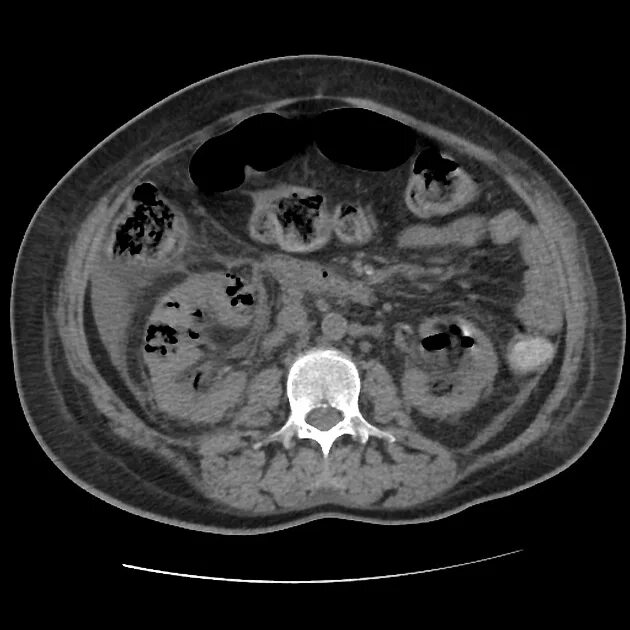

Пиелонефрит кт